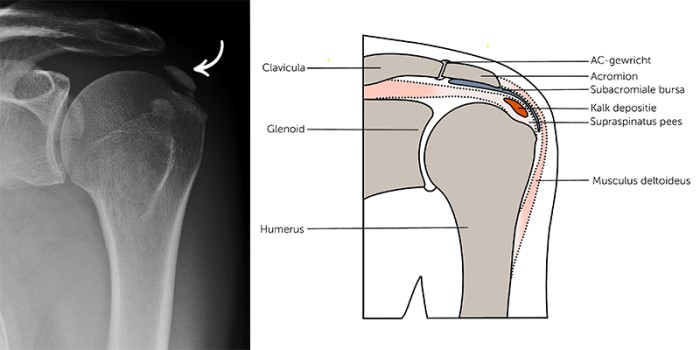

Patiënten die ondanks conservatieve behandeling klachten bleven houden, kregen voorheen altijd een chirurgische behandeling. Via een (kijk)operatie van de schouder worden dan de geïrriteerde slijmbeurs en de verkalking in de pees verwijderd. Aan zo’n ingreep kleven echter ook belangrijke nadelen en daarom zijn er minder invasieve behandelingen ontwikkeld [figuur 2]. Voorbeelden hiervan zijn shockwave-therapie en barbotage (ook wel ultrasound-guided needling genoemd).1112

Figuur 2 | Een schematische weergave van een behandeling met hoogenergetische shockwavetherapie (links) en barbotage (rechts).

Een schematische weergave van een behandeling met hoogenergetische shockwavetherapie (links) en barbotage (rechts).

Bij shockwavetherapie worden het peesweefsel en het kalkdepot behandeld met drukgolven (radiaire shockwavetherapie, RSWT) of met geluidsgolven (extracorporale ‘focussed’ shockwavetherapie, ESWT), waarbij de laatste verder kan worden verdeeld in hoogenergetische en laagenergetische ESWT. ESWT kan zorgen voor fragmentatie van de verkalking, een verbetering van de doorbloeding en vermindering van de ontstekingsfactoren in het peesweefsel, wat de pijn vermindert.

Bij barbotage wordt de verkalking echogeleid herhaaldelijk aangeprikt en daardoor gefragmenteerd. Zo nodig wordt de pees daarna gespoeld met fysiologisch zout om de kalkmineralen zo veel mogelijk te verwijderen. Deze procedure wordt doorgaans gecombineerd met een corticosteroïdinjectie in de bursa, om de eventuele pijn in de eerste paar weken na de ingreep onder controle te houden.